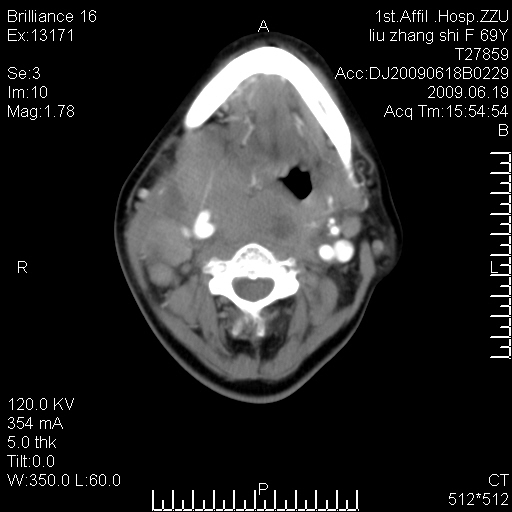

标题: CT26782:女,69岁,颈部占位,3天后公布病理结果。

【病理证实系列】女,69岁,颈部占位,有病理结果,3天后公布。(由于病例时间较久,临床资料不全,请网友见谅)本系列将有几百种常见、少见及罕见病例,均经病理证实。病例资料来自郑州大学第一附属医院。与网友共享,本人有空就发。

甲状腺癌并颈部淋巴结转移。感谢楼主的良苦用心,谢谢。

甲状腺癌并颈部淋巴结转移。

需与鼻咽癌鉴别!

支持甲状腺癌广泛侵及周围结构并颈部淋巴结转移。

鉴别:淋巴瘤、恶性神经源性病变、恶性纤维组织细胞瘤。

病理结果:颈部非霍奇金淋巴瘤。

右侧甲状腺确实有问题